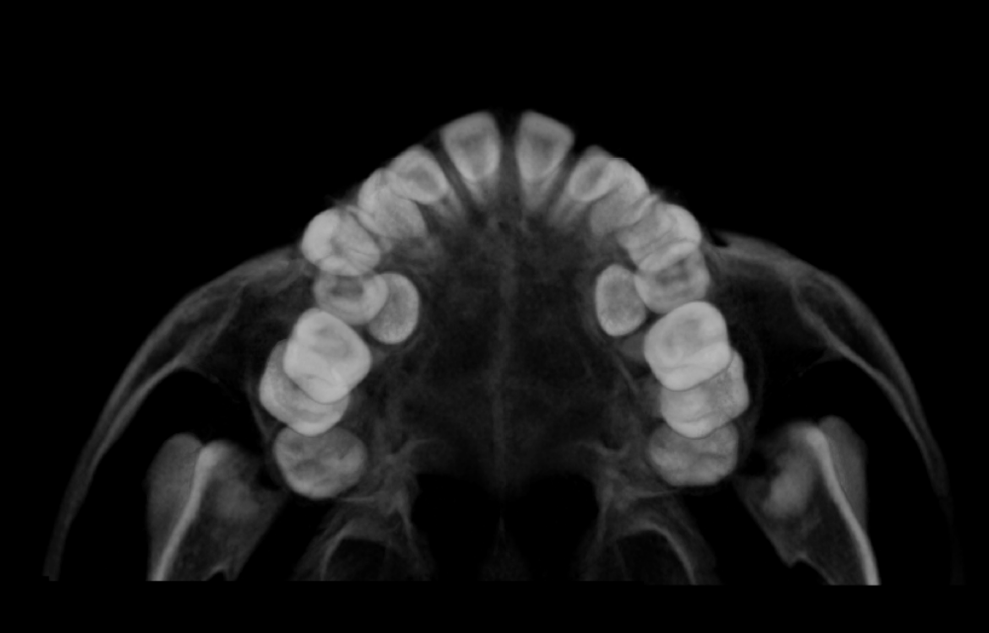

• Panoramic images are digital 2D dental x-ray examinations that captures the teeth, jaws and TMJs in a single image. The panoramic is an overview image that is used to visualize erupted and unerupted teeth, evaluate root alignment, TMJ’s and the sinuses.